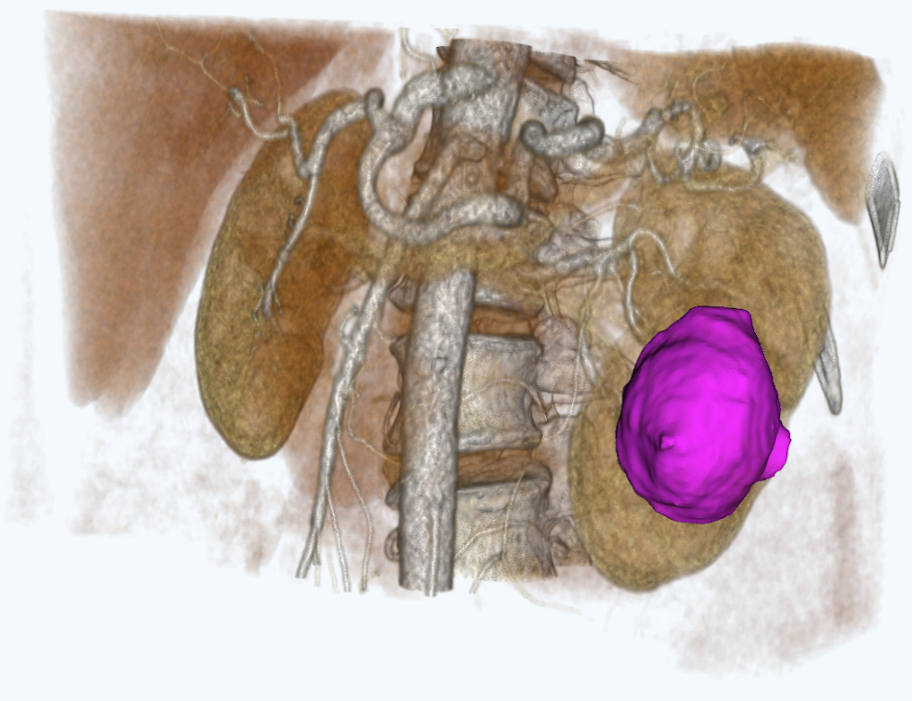

для планирования оперативного вмешательстваСервис создает интерактивные виртуальные 3D модели пациента на основе снимков компьютерной томографии

Персонализированная анатомия

Сервис позволяет выделить расположение артерий, вен, мочеточников, новообразований и паренхимы почки пациента.

Работа с 3D моделью

Врач может работать с 3D моделью для изучения анатомических особенностей пациента